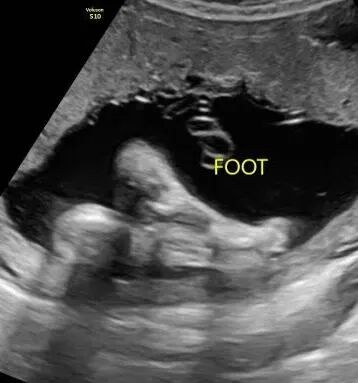

宝宝接近四个月的时候,爱妈Y再次进行了B超检查,此次检查清晰显示出一个健康可爱的女宝宝。爱妈随即将B超照片发送给准妈妈,并满心欢喜地赞叹宝宝的可爱。看到宝宝健康成长,准妈妈既感动又高兴,对爱妈的细心照料表示深深的感激。 准父母成功匹配后,我们会为双方建立一个交流群,这样准父母和爱妈可以方便地进行沟通。在这个群里,爱妈和我们的客服团队会定期更新检查结果和宝宝的成长情况。我们都非常期待下次见到宝宝的时刻!